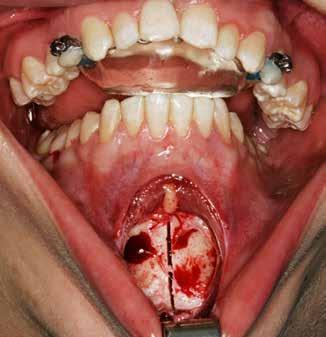

Klik ind på Tandlægebladet.dk og opret en reklamation, så sørger vi for, at bladet lander i din postkasse.

Klik ind på Tandlægebladet.dk og vælg om os

BAGGRUND – Transverselle okklusionsafvigelser kombineret med en vækstbetinget kæbedeformitet korrigeres sædvanligvis ved en sektioneret Le Fort 1-osteotomi eller kirurgisk assisteret ganeekspansion. Ved ekstreme transverselle skeletale diskrepanser mellem maksillen og mandiblen kan der være indikation for transversel udvidelse af mandiblen ved hjælp af mandibulær midtlinjeosteotomi eller mandibulær midtlinjedistraktionsosteogenese.

PATIENTTILFÆLDE – En 15-årig dreng med infantil autisme blev henvist fra Hjørring Kommunes Tandpleje til Kæbekirurgisk Afdeling, Aalborg Universitetshospital, for ortodontisk-kirurgisk behandling af et stort horisontalt maksillært overbid uden kontakt på nogen af tænderne. Den vækstbetingede kæbedeformitet blev korrigeret ved hjælp af ortodonti og mandibulær midtlinjedistraktionsosteogenese efterfulgt af en sektioneret Le Fort I-osteotomi og bilateral sagittal splitosteotomi.

KONKLUSION – Mandibulær midtlinjedistraktionsosteogenese er en forudsigelig behandlingsmodalitet til transversel udvidelse af mandiblen. Imidlertid er behandlingen forbundet med en betydelig risiko for recidiv samt biologiske og tekniske komplikationer, hvorfor mandibulær midtlinjedistraktionsosteogenese udelukkende anbefales til korrektion af ekstreme vækstbetingede transverselle okklusionsafvigelser.

EMNEORD Jaw abnormalities | malocclusion | orthodontics | orthognathic surgery

PERNILLE SAGBAKKEN, tandlæge, Odontologisk Institut, Det Sundhedsvidenskabelige Fakultet, Københavns Universitet

ANNETTE DALGAARD KJELLERUP, specialtandlæge i ortodonti, Kæbekirurgisk Afdeling, Aalborg Universitetshospital